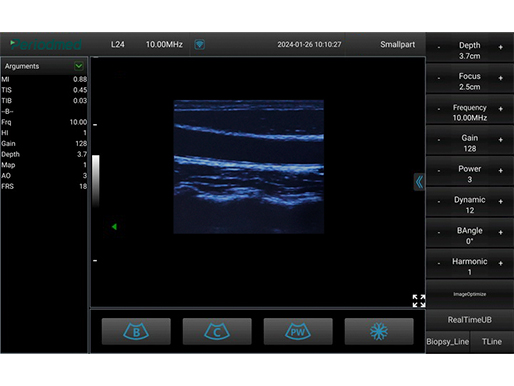

线阵探头-B模式-颈动脉